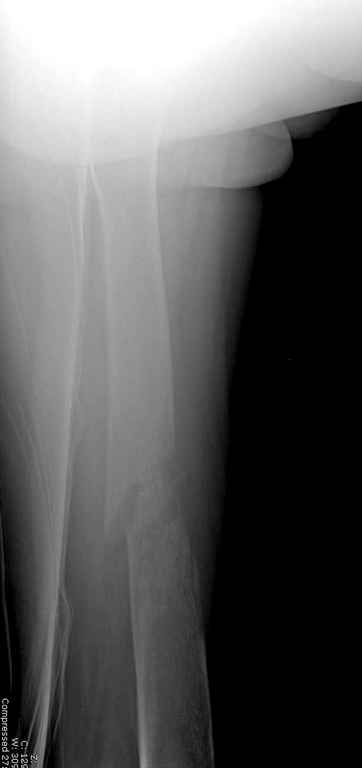

Здесь случай 66 летней пациентки со спонтанными болями в левой нижней конечности, обратилась в приемное, сделаны снимки бедра и КТ.

Патологический перелом бедра, конечность на вытяжении.

Со слов, больная ничем не болела, только последние 3 месяцев чувствовала боли в бедренной области. КТ брюшной полости подтвердил увеличенную правую почку. (5-6)